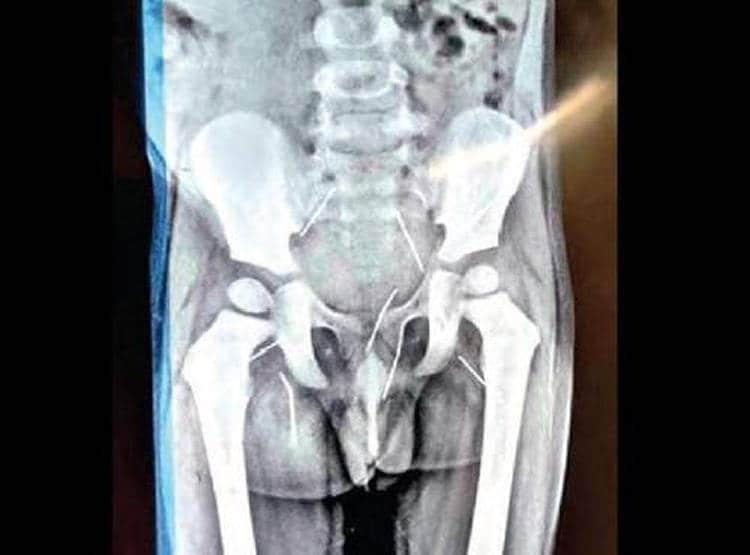

दर्द से तड़प रहा था बच्चा, X Ray में निकलीं 11 सुइयां

तेलंगाना में 3 साल के बच्चे के शरीर में 11 सुइयां निकली है. यह बच्चा 6 महीने से पेट में दर्द से परेशान था. लेकिन घर के लोग घरेलू इलाज और साधारण दवाइयां देकर पेट दर्द से राहत दिला दे रहे थे. (प्रतीकात्मक तस्वीर)

लेकिन जब समस्या बढ़ गई और बच्चा दर्द से लगातार रोता रहा तो परिजनों ने डॉक्टर को दिखाया. डॉक्टर ने जब बच्चे का एक्स रे देखा तो उनके होश उड़ गए.

बच्चे के पीठ, पिछले हिस्से और प्राइवेट पार्ट के आसपास 11 सिलाई वाली सुइयां थीं. (प्रतीकात्मक तस्वीर)

जब बच्चे को डॉक्टर श्रीनिवास रेड्डी ने देखा तो उन्होंने एक्सरे कराया. एक्सरे में पता चला कि बच्चे के शरीर में 11 सुइयां हैं.

डॉक्टर श्रीनिवास रेड्डी ने ऑपरेशन करके बच्चे के शरीर से 8 सुइयां निकाल दी हैं. बाकी तीन सुइयां बाद में निकाली जाएंगी. अभी बच्चे की हालत स्थिर है. (प्रतीकात्मक तस्वीर)